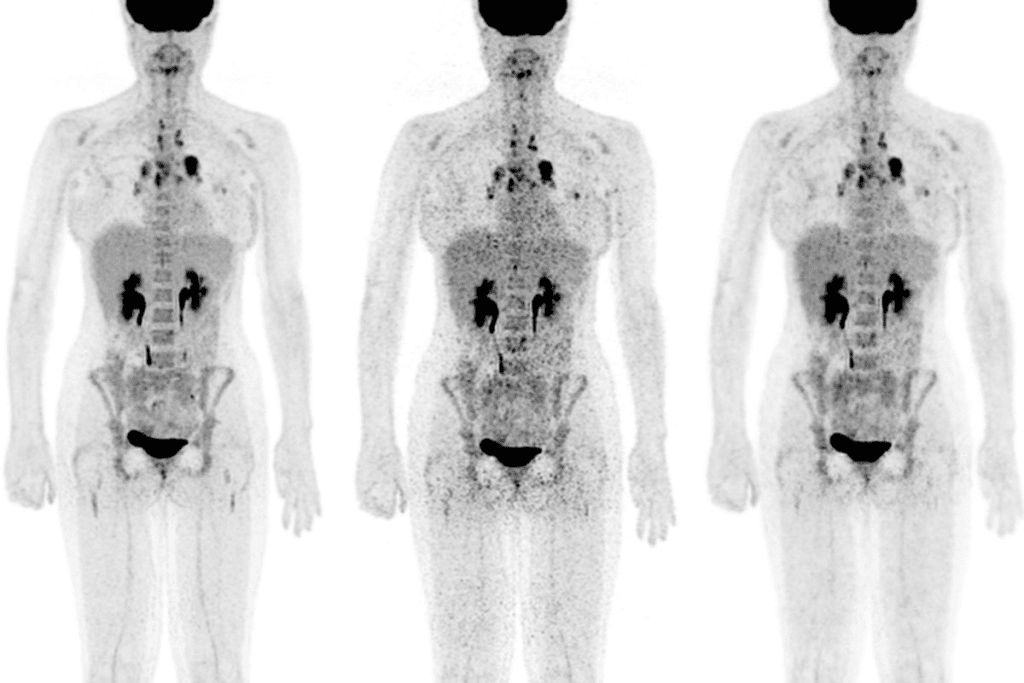

PET scans are very useful for finding cancers, but they’re not perfect. About 10% of cancers can’t be seen on PET scans. This is because some cancers don’t use a lot of energy, making them hard to spot.

PET scans work by showing where cancer cells are by using a special sugar called Fluorodeoxyglucose (FDG). But, not all cancers use a lot of energy. This means they can’t be seen as clearly.

Cancers Not Visible on PET Scans

Not all cancers can be seen on PET scans. It’s important to know which ones can’t for better cancer care. PET scans use a glucose analog to show active tissues. But, some cancers don’t use enough glucose or have other traits that hide them from PET scans.

Overview of PET-Negative Malignancies

PET-negative malignancies are cancers that don’t show up on PET scans. This is because they don’t take in enough FDG. These cancers might have low metabolic rates or use different metabolic paths. This makes them hard to spot on PET scans, leading to challenges in diagnosis and staging.

Some cancers that are hard to see on PET scans include certain prostate cancers, kidney cancers, and some cancers in the gut. These cancers have unique traits that make them hard to spot.